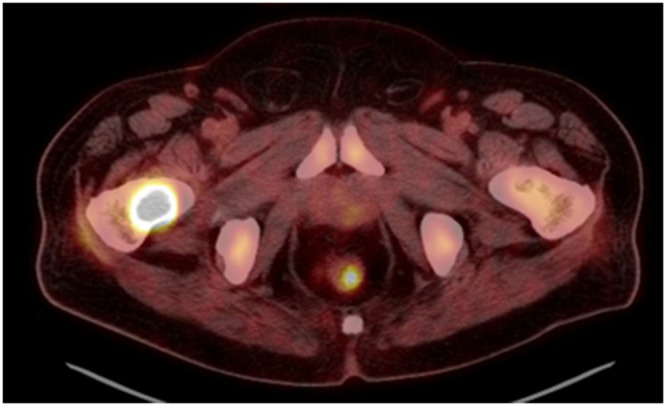

骨骼是转移性疾病的第三大常见部位。治疗很少能治愈;相反,它寻求控制疾病进展和缓解症状。对有转移性骨病症状的患者的影像学评估应从x线平片开始。进一步的成像包括PET -CT扫描和骨显像的结合。我们建议在影像学检查后进行活检。转移性骨病的治疗方法包括全身治疗、放射治疗(RT)和手术。外束放射治疗(EBRT)用于骨折稳定后疼痛控制和术后治疗。单分数和多分数方案同样有效地实现疼痛控制。对即将发生骨折的患者进行充分的骨折风险评估,以指导患者做出稳定骨折的决定。尽管特异性较低,但普通x光片是确定即将发生骨折风险的首选工具。CT扫描具有较高的阳性预测值,可增加诊断价值。手术处理取决于患者的特点、肿瘤类型和骨折/骨的位置。固定选择包括钢板和螺钉固定、髓内钉和内假体。尽管广泛使用,但由于长柄的并发症发生率较高,因此需要对每个患者单独分析整个股骨的预防性稳定。

Bones are the third most common site of metastatic disease. Treatment is rarely curative; rather, it seeks to control disease progression and palliate symptoms. Imaging evaluation of a patient with symptoms of metastatic bone disease should begin with plain X-rays. Further imaging consists of a combination of (PET)-CT scan and bone scintigraphy. We recommend performing a biopsy after imaging workup has been conducted. Metastatic bone disease is managed with a combination of systemic treatment, radiotherapy (RT), and surgery. External beam RT (EBRT) is used for pain control and postoperatively after fracture stabilization. Single-fraction and multiple-fractions schemes are equally effective achieving pain control. Adequate assessment of fracture risk should guide the decision to stabilize an impending fracture. Despite low specificity, plain X-rays are the first tool to determine risk of impending fractures. CT scan offers a higher positive predictive value and can add diagnostic value. Surgical management depends on the patient's characteristics, tumor type, and location of fracture/bone stock. Fixation options include plate and screw fixation, intramedullary (IM) nailing, and endoprostheses. Despite widespread use, the need for prophylactic stabilization of the entire femur should be individually analyzed in each patient due to higher complication rates of long stems.